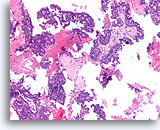

Ductaal carcinoom, Mannenborst FNA, celblok.

Hooggradige nucleaire atypie, necrotisch materiaal, discohesie en vrije stratificatie kunnen worden waargenomen.

60X

Ductaal carcinoom, Mannenborst FNA, celblok.

Hooggradige nucleaire atypie, necrotisch materiaal, discohesie en vrije stratificatie kunnen worden waargenomen.

60X